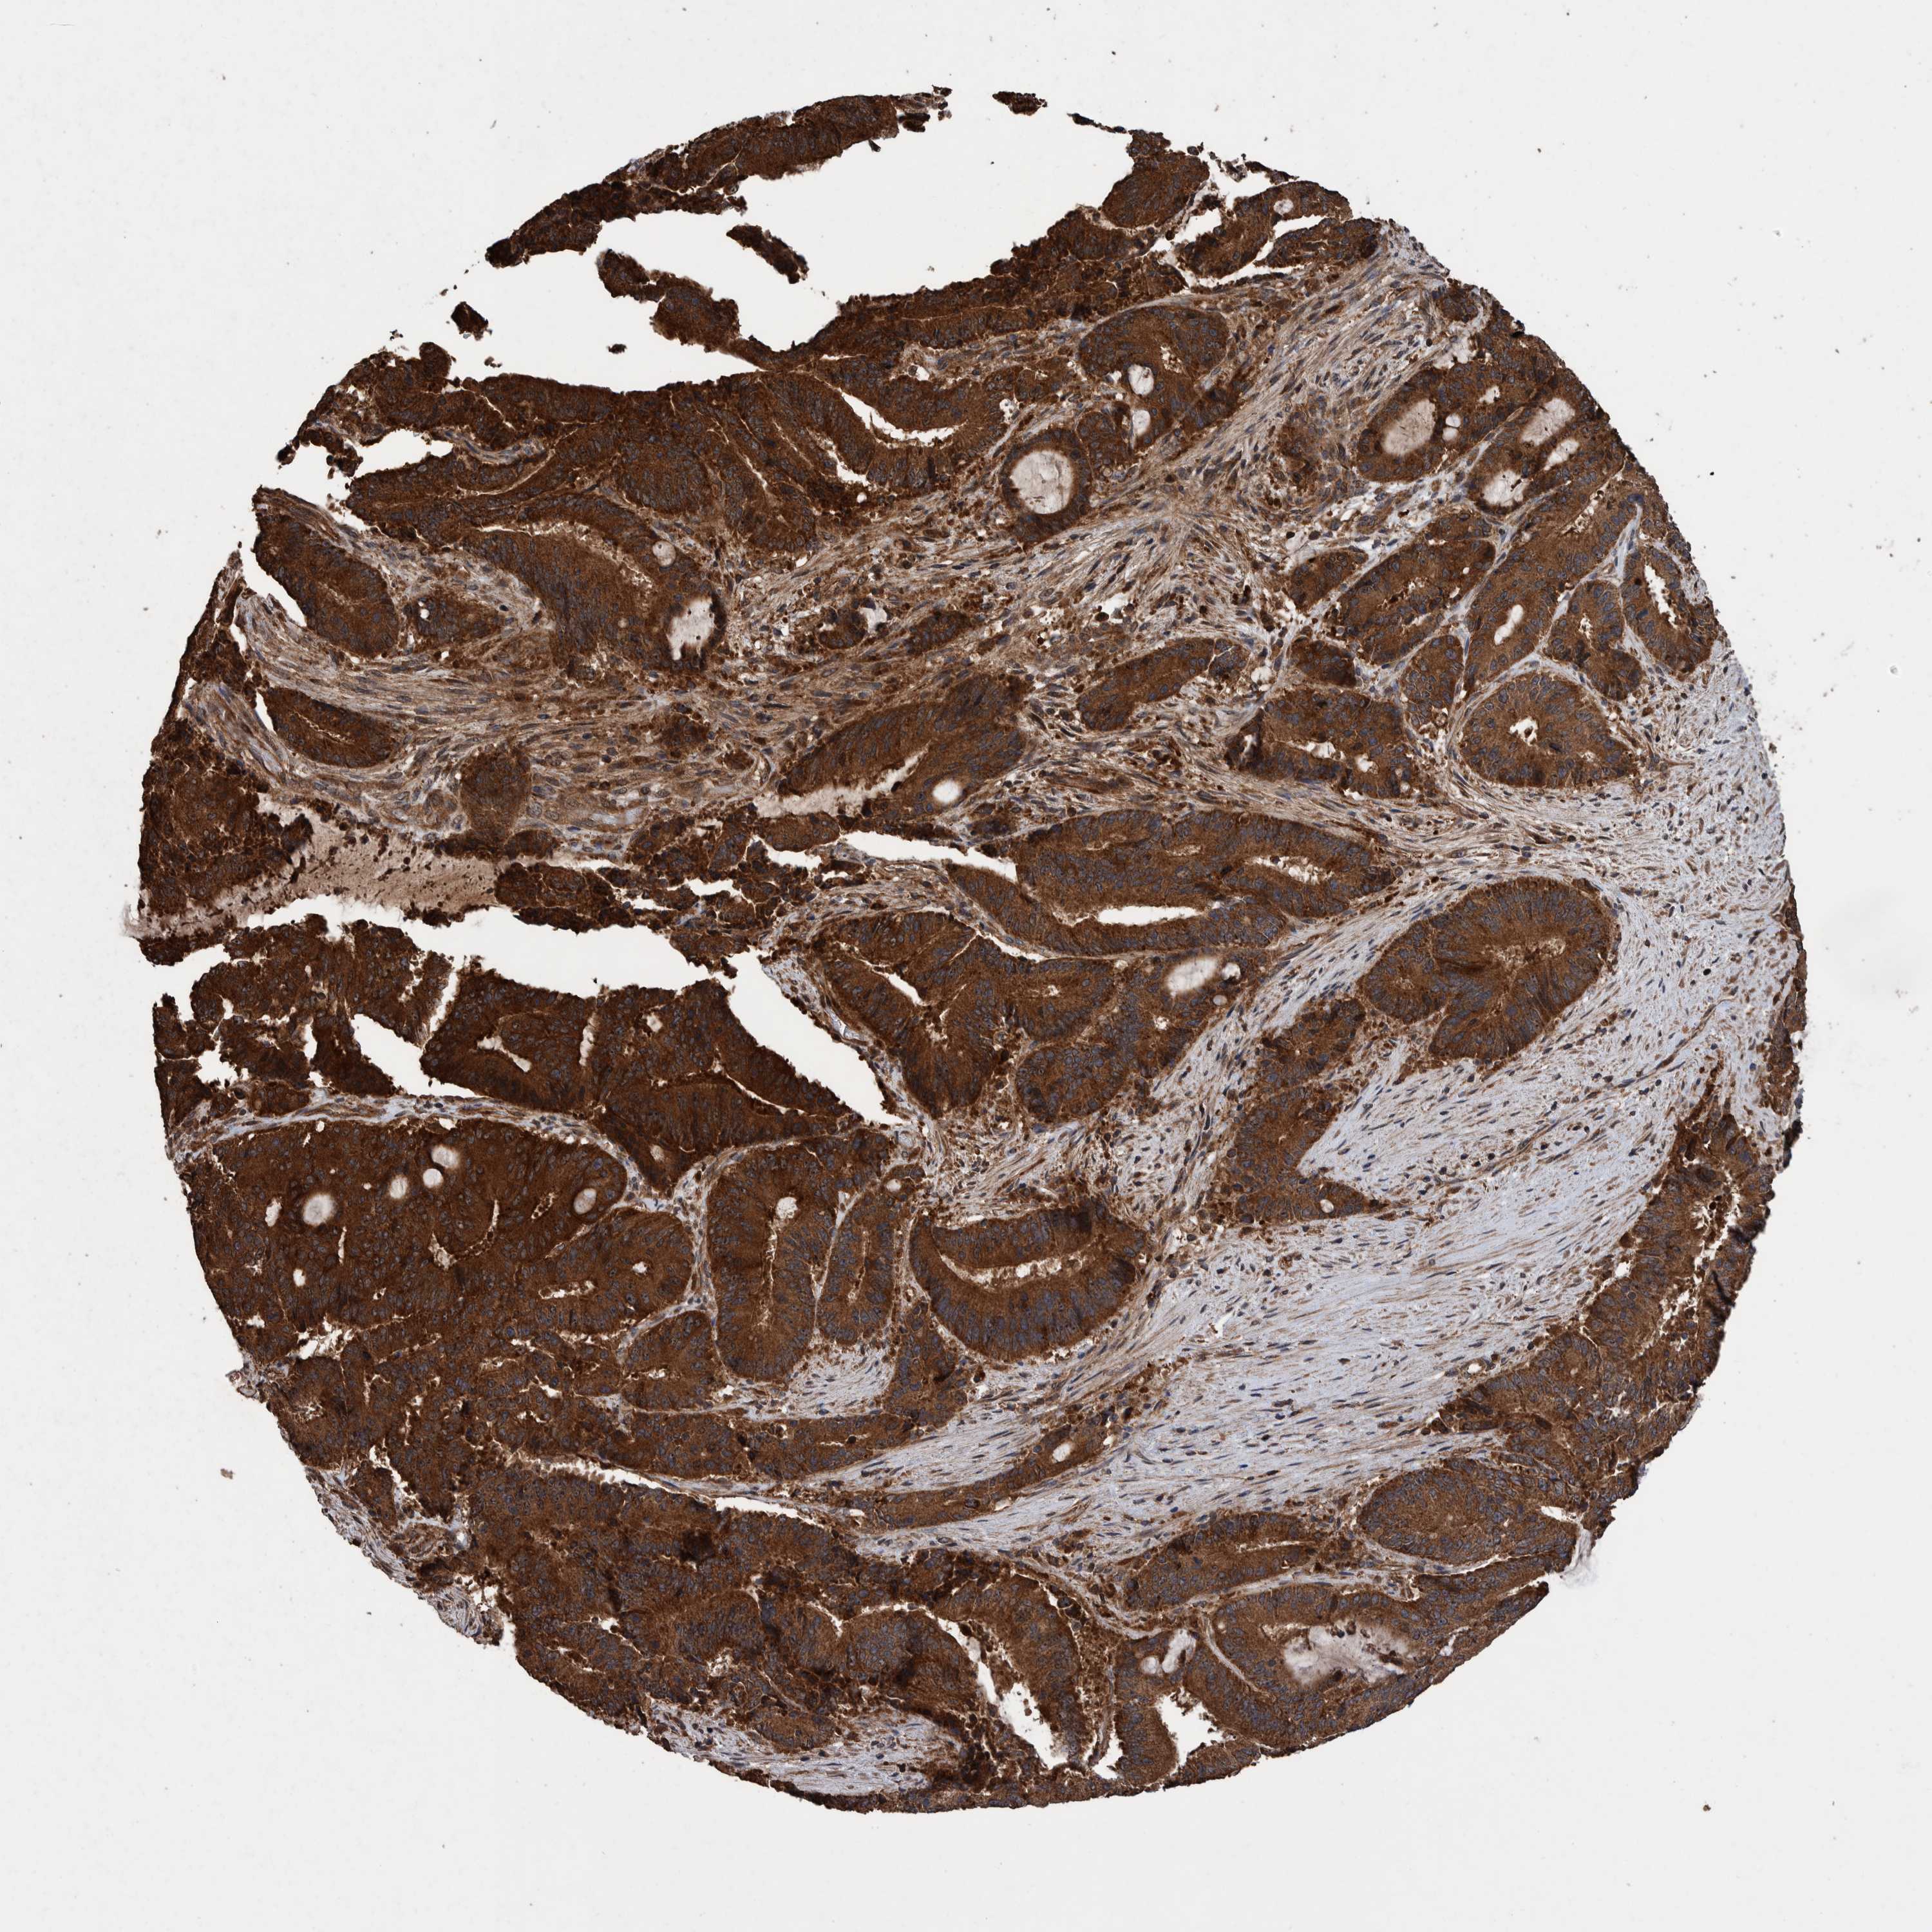

LIVER CANCER - Protein expressioni

A mouse-over function shows sample information and annotation data. Click on an image to view it in a full screen mode. Samples can be filtered based on level of antibody staining by selecting one or several of the following categories: high, medium, low and not detected. The assay and annotation is described here.

Note that samples used for immunohistochemistry by the Human Protein Atlas do not correspond to samples in the TCGA dataset.

Antibody stainingi

Antibody staining in the annotated cell types in the current human tissue is reported as not detected, low, medium, or high, based on conventional immunohistochemistry profiling in selected tissues. This score is based on the combination of the staining intensity and fraction of stained cells.

Each image is clickable and will lead to virtual microscopy that enables deeper exploration of all samples and also displays staining intensity scores, fraction scores and subcellular localization as well as patient and tissue information for each sample.

Antibody HPA023623

Antibody HPA066431

Staining

High

Medium

Low

Not detected

Intensity

Strong

Moderate

Weak

Negative

Quantity

>75%

75%-25%

<25%

None

Location

Nuclear

Cytoplasmic/membranous

Cytoplasmic/membranous,nuclear

Cholangiocarcinoma

Carcinoma, Hepatocellular, NOS